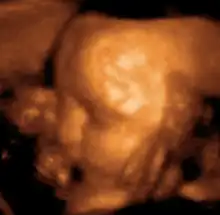

Medical ultrasound is an ultrasound-based diagnostic medical imaging technique used to visualize muscles, tendons, and many internal organs to capture their size, structure and any pathological lesions with real time tomographic images. Ultrasound has been used by radiologists and sonographers to image the human body for at least 50 years and has become a widely used diagnostic tool. The technology is relatively inexpensive and portable, especially when compared with other techniques, such as magnetic resonance imaging (MRI) and computed tomography (CT). Ultrasound is also used to visualize fetuses during routine and emergency prenatal care. Such diagnostic applications used during pregnancy are referred to as obstetric sonography. As currently applied in the medical field, properly performed ultrasound poses no known risks to the patient.[29] Sonography does not use ionizing radiation, and the power levels used for imaging are too low to cause adverse heating or pressure effects in tissue.[30][31] Although the long-term effects due to ultrasound exposure at diagnostic intensity are still unknown,[32] currently most doctors feel that the benefits to patients outweigh the risks.[33] The ALARA (As Low As Reasonably Achievable) principle has been advocated for an ultrasound examination – that is, keeping the scanning time and power settings as low as possible but consistent with diagnostic imaging – and that by that principle nonmedical uses, which by definition are not necessary, are actively discouraged.[34]

According to RadiologyInfo,[36] ultrasounds are useful in the detection of pelvic abnormalities and can involve techniques known as abdominal (transabdominal) ultrasound, vaginal (transvaginal or endovaginal) ultrasound in women, and also rectal (transrectal) ultrasound in men.